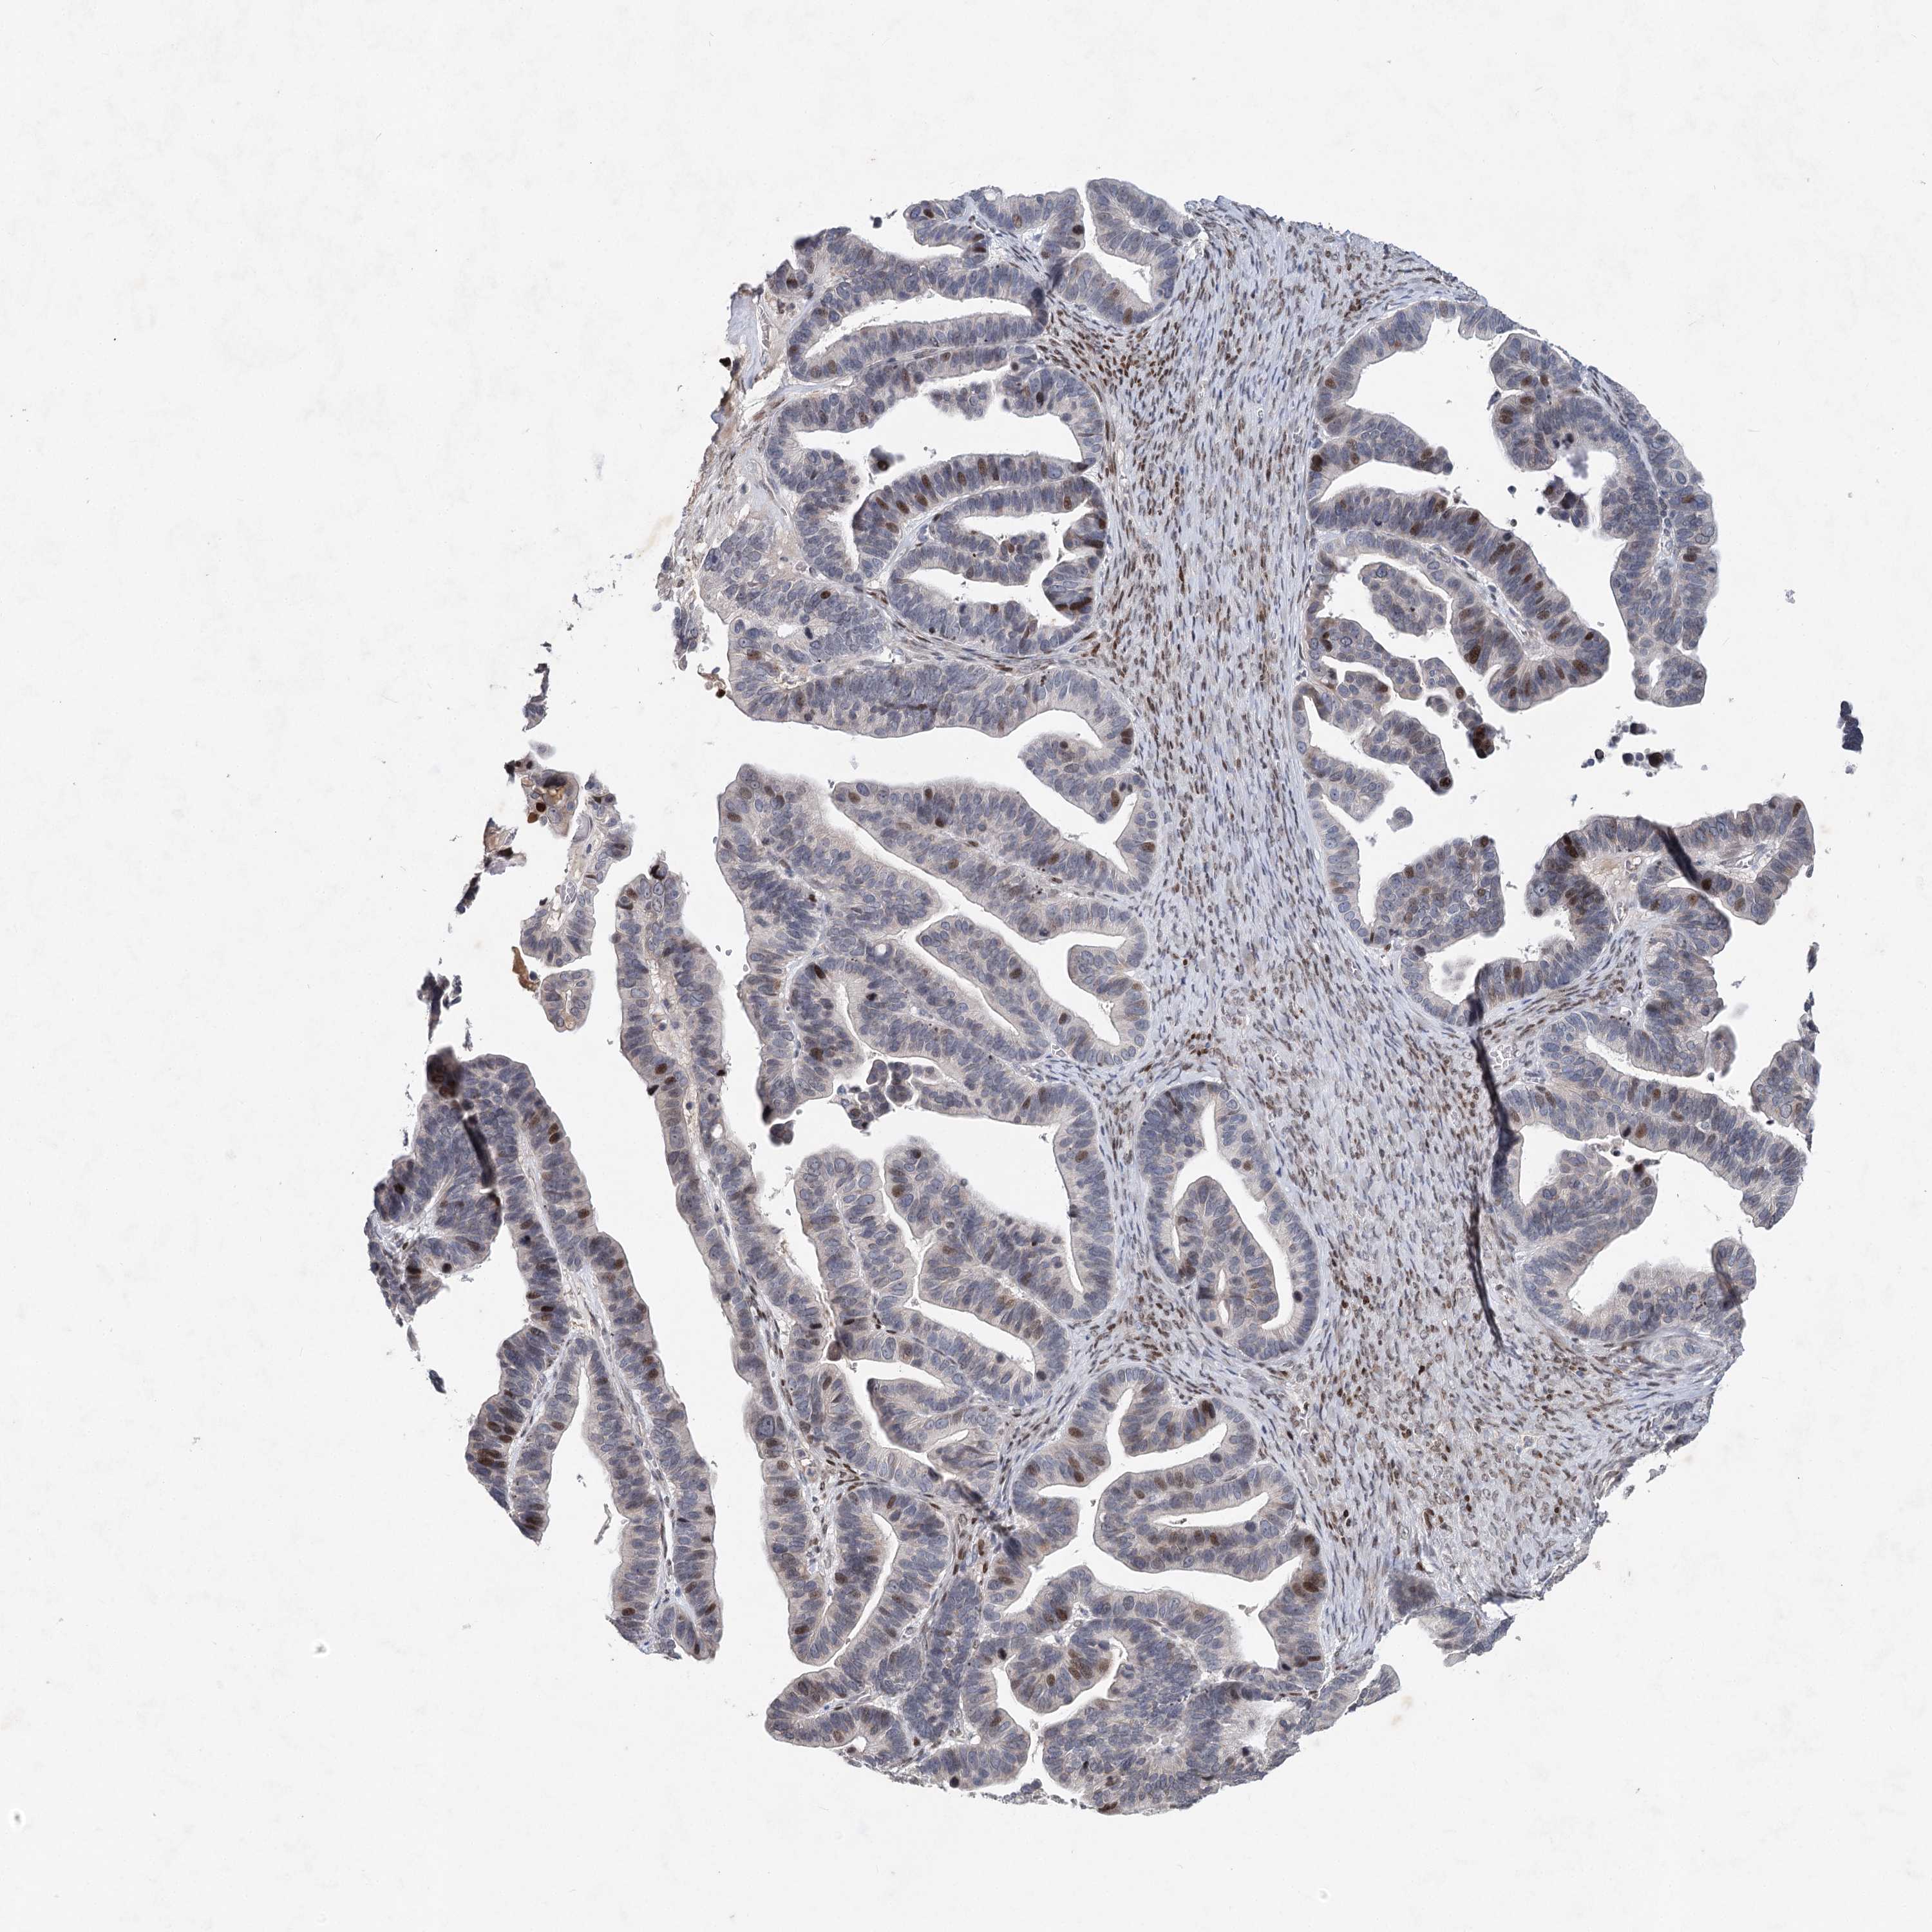

OVARIAN CANCER - Protein expressioni

A mouse-over function shows sample information and annotation data. Click on an image to view it in a full screen mode. Samples can be filtered based on level of antibody staining by selecting one or several of the following categories: high, medium, low and not detected. The assay and annotation is described here.

Note that samples used for immunohistochemistry by the Human Protein Atlas do not correspond to samples in the TCGA dataset.

Antibody stainingi

Antibody staining in the annotated cell types in the current human tissue is reported as not detected, low, medium, or high, based on conventional immunohistochemistry profiling in selected tissues. This score is based on the combination of the staining intensity and fraction of stained cells.

Each image is clickable and will lead to virtual microscopy that enables deeper exploration of all samples and also displays staining intensity scores, fraction scores and subcellular localization as well as patient and tissue information for each sample.

Antibody HPA038449

Staining

High

Medium

Low

Not detected

Intensity

Strong

Moderate

Weak

Negative

Quantity

>75%

75%-25%

<25%

None

Location

Nuclear

Cytoplasmic/membranous

Cytoplasmic/membranous,nuclear

Cystadenocarcinoma, serous, NOS

Carcinoma, endometroid

Cystadenocarcinoma, mucinous, NOS

Carcinoma, NOS